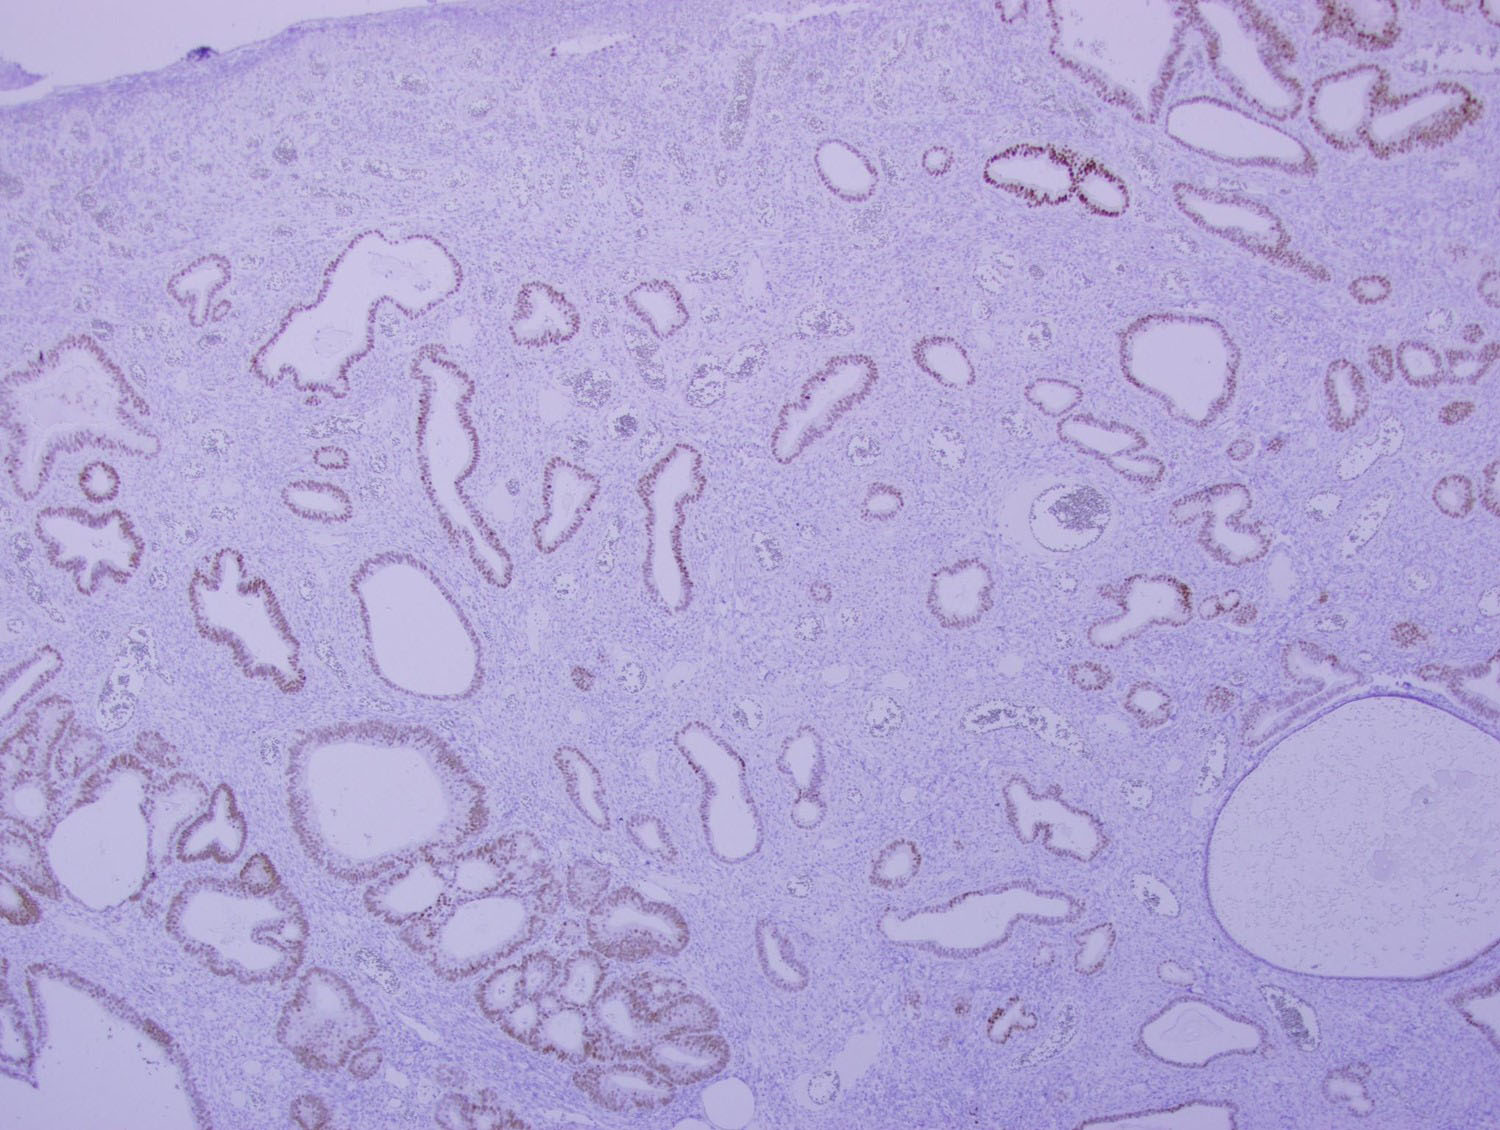

Microscopic examination of the sigmoid polyp demonstrated complete replacement of the normal colonic mucosa with infiltrating angulated and irregular glands lined by benign pseudostratified columnar epithelium, some of which were cystically dilated (Figures 2-4). Surrounding these glands was a characteristic spindle cell stroma admixed with inflammatory cells and prominently dilated vasculature. Immunohistochemical (IHC) stains were performed. The glands were negative for CDX2 and CK20 (Figures 5 and 6), while positive for PAX8 (Figure 7) and focally strongly positive for CK7 (Figure 8). The surrounding stroma was focally positive for CD10 (Figure 9).